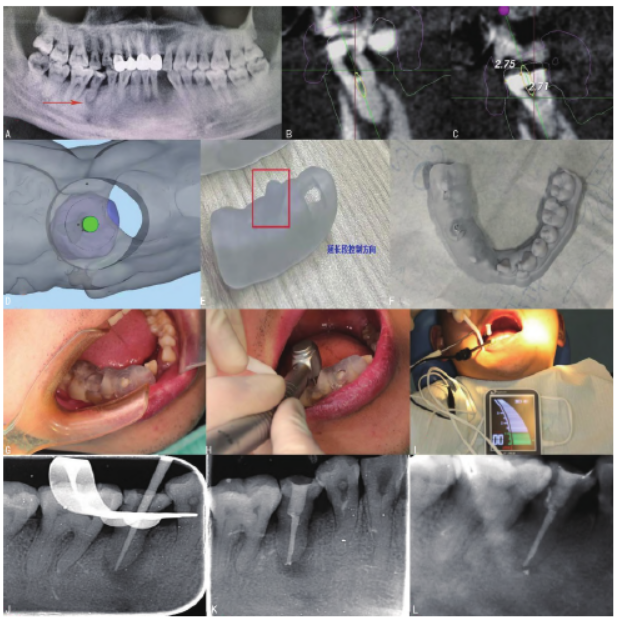

口腔全景片示:45冠方充填影像累及髓腔,牙周膜增宽,牙槽骨吸收至根中1/3,根中1/3根管影像模糊不清,近中及根尖周低密度影像(图1A)。诊断:45慢性根尖周炎,45牙髓钙化,慢性牙周炎。

45根管非手术治疗后择期修复治疗,牙周治疗。患者知情同意后,全口行洁治术。术前橡皮障隔湿,去除冠部充填物,去净腐质,1%次氯酸钠溶液与0.9%氯化钠溶液交替冲洗髓腔,DG16探针探及根管口,使用8#K 锉与乙二胺四乙酸(EDTA)以最小的垂直压力未能疏通根管,为避免破坏更多健康牙体组织,进行CBCT检查及获取口内模型,利用数字化导板设计软件进行分析,测量实际根管口位置的距离、根管长度、钙化牙本质的厚度及根管弯曲度(图1B、C)。

设计出适合此根管的车针及套筒,随后进行导板制作及试戴(图1D~H)。术中配套车针及10#Kprotape镍钛根管锉在导板引导下到达工作长度,根尖定位仪确定工作长度(图1I),常规根管疏通,根管预备,预备完成后,拭干根管,封氢氧化钙糊剂,Caviton暂封窝洞。

2周后复诊,45暂封物完好、无自觉症状、无叩痛、根管内无异味、无渗出物,冲洗根管,纸尖拭干,试尖(图1J),连续波热牙胶垂直加压技术充填根管,术后根尖X线片显示根管恰填(图1K)。

术后6个月复查,患牙无临床症状和阳性体征,患牙咀嚼功能正常,患者满意,根尖X线片示根尖周低密度影像范围减小(图1L)。

图1 口腔全景片。注:A为术前全景片;B、C为CBCT下45根管内可见钙化组织;D、E为CBCT导航下结合3D打印技术设计数字化导板;F为模型上试戴导板;G为患者口内试戴导板;H为在导板引导下疏通钙化根管;I为根管测量仪定工作长度;J为试尖;K为术后即刻45根尖X线片;L为术后6个月45根尖X线片。